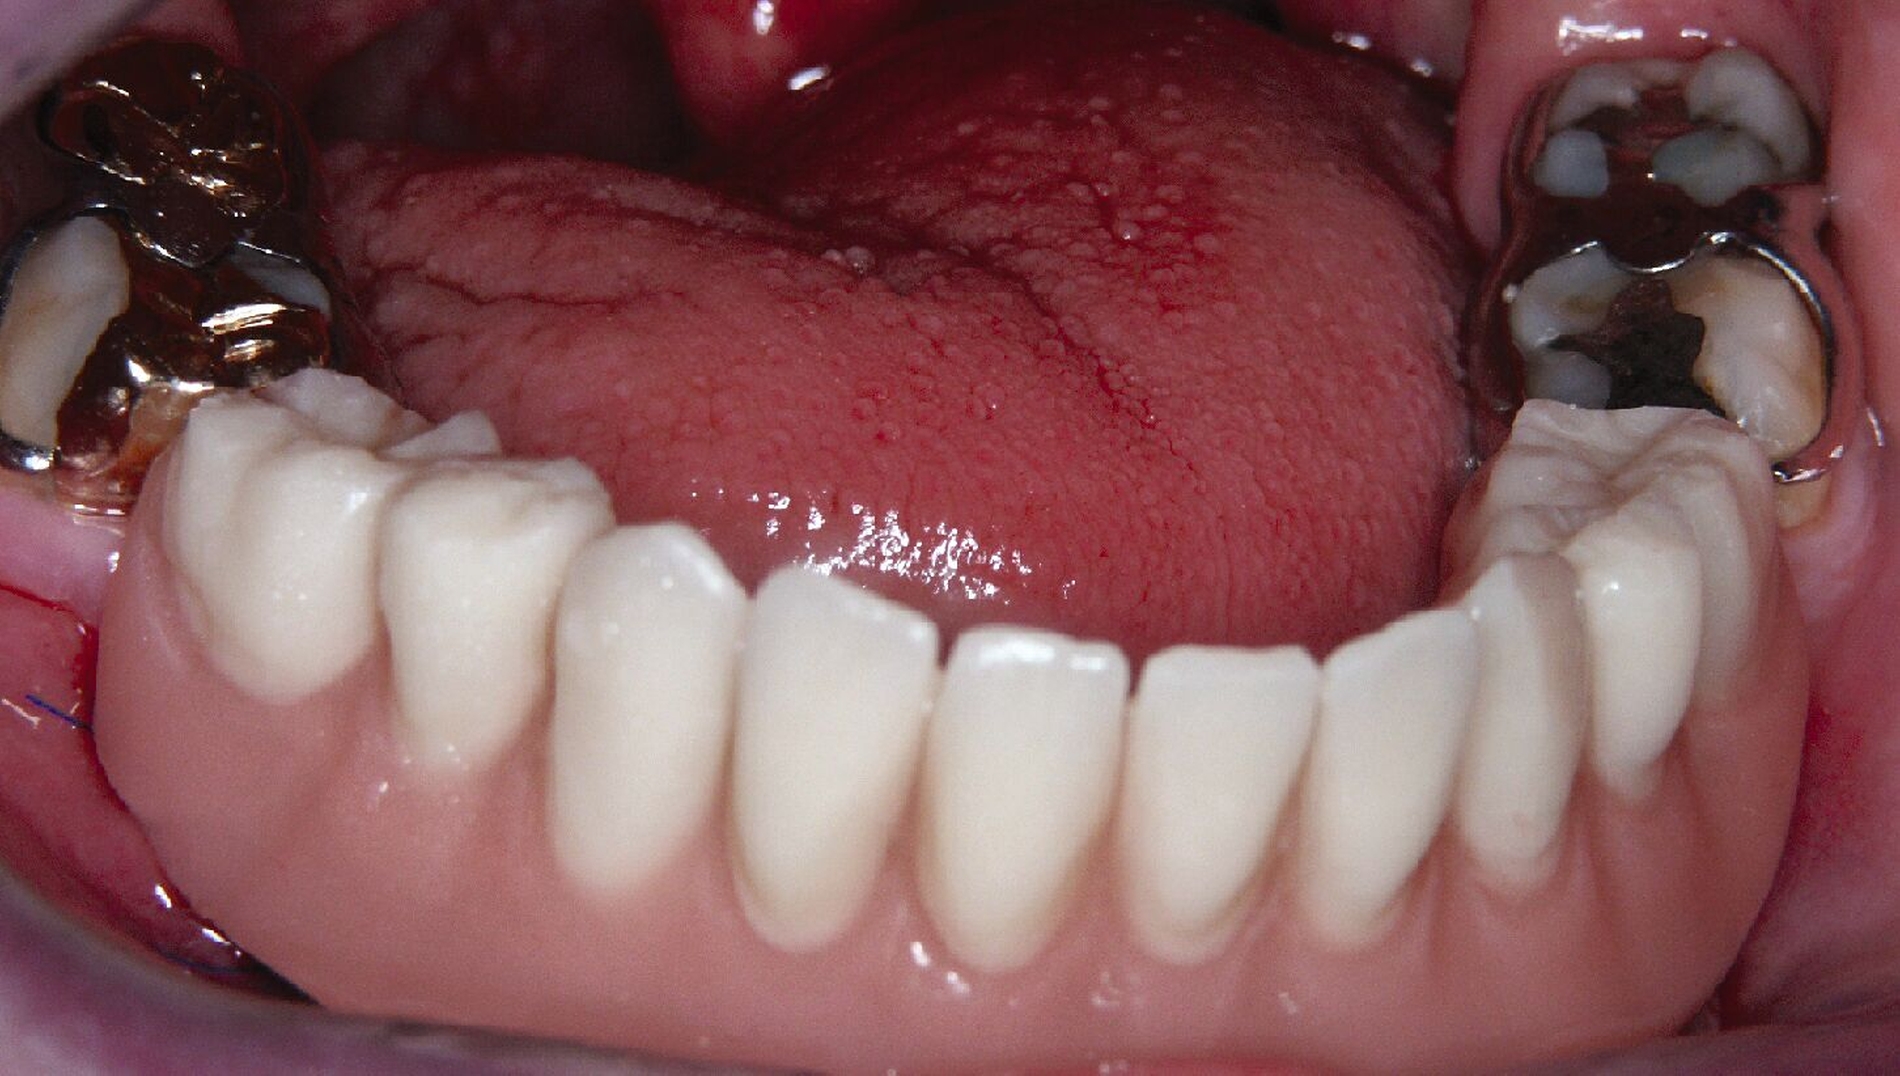

Nachdem der Patient bei einem Berufsunfall mit Ausnahme der zweiten Molaren und der Weisheitszähne alle Zähne im Unterkiefer verloren hatte, erfolgte 1996 im Alter von 44 Jahren die definitive Lückenversorgung. Hierzu wurden eine verschraubte Brückenkonstruktion (044-034-043-044) sowie zwei verblockte Kronenpaare auf insgesamt acht Implantaten eingesetzt. Nach sieben Jahren Tragedauer wurde an mehreren Implantaten röntgenologisch ein Knochenabbau festgestellt. Verkürzte Kontrollintervalle mit professionellen Zahnreinigungen und intensiven Instruktionen zur Interdentalhygiene konnten nicht verhindern, dass nach weiteren sieben Jahren Anfang 2011 der Knochenverlust an den meisten Implantaten auf 50 bis 80 Prozent zunahm (Abb. 1a).

Die Entscheidung zur Explantation fiel wegen des beschleunigten Knochenverlusts und der extrem erschwerten Bedingungen für eine effektive Mundhygiene im Bereich der Implantate mit Sondierungstiefen bis zu 12 mm (Abb. 1b und 1c). Unter Lokalanästhesie wurden sieben der acht Implantate mit einem passenden Trepanbohrer mit 0,1 mm Aufmaß im Vergleich zum Außendurchmesser der Implantate umbohrt, anschließend mit einem kleinen Rasparatorium gelockert und dann mit einer Arterienklemme entfernt. Entscheidend für die Eignung der Trepanbohrer war die Längenmarkierung, um eine Nervverletzung bei der Entfernung der sehr tief gesetzten Seitenzahnimplantate zu vermeiden (Abb. 1d und 1e). Eine ausgedehnte Lappenbildung konnte durch dieses Vorgehen vermieden werden.

Eine präoperativ vorbereitete Interimsprothese, die über zwei gegossene Bonwill-Klammern sowie das verbliebene Implantat in regio 35 stabil abgestützt war, diente gleichzeitig als Verbandsplatte (Abb. 1f). Auf eine Glättung scharfer Knochenkanten oder die Nivellierung der Kieferkämme wurde verzichtet, um einen iatrogenen Knochenverlust zu vermeiden und das regenerative Potenzial des verbliebenen Knochens zu nutzen (Abb. 1g). Bereits bei der röntgenologischen Kontrolle nach drei Monaten war eine deutliche Zunahme des Knochens im Bereich der alten Implantatpositionen zu erkennen (Abb. 1h). Eine Nachimplantation von vier Implantaten in den Positionen 32, 34, 42 und 44 erfolgte neun Monate nach der Explantation und einer vorangegangenen Verbesserung der Weichgewebsbedeckung durch multiple freie Schleimhautransplantate vom harten Gaumen. Die knöcherne Regeneration unter der gut abgestützten Modellgussprothese verlief so günstig, dass sich der vertikale Höhenverlust des Alveolarkamms im Bereich der gescheiterten Implantate auf circa 2 mm begrenzen ließ. Das zur Entlastung der Kieferkämme und der einheilenden Implantate außerordentlich hilfreiche Implantat in regio 35 wurde erst nach dem Einheilen der nachgesetzten Implantate entfernt. Nach der Einheilzeit der Implantate von weiteren drei Monaten wurde eine kombiniert Zahn/Implantat-gestützte Teleskopprothese mit intraoral verklebten Galvano-Sekundärkronen eingegliedert (Abb. 1k bis 1m). Inzwischen ist diese, wie eine herausnehmbare Brücke abgestützte UK-Prothese seit zehn Jahren funktionstüchtig ohne Zeichen einer Periimplantitis an den vier Implantaten.